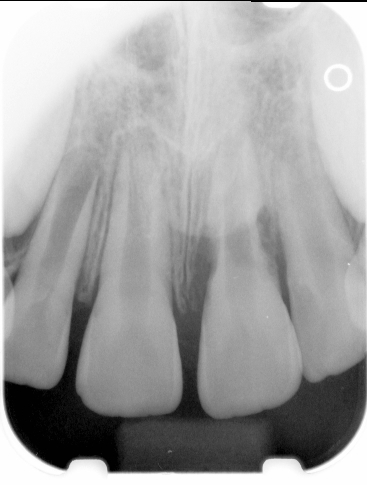

Fig 1. Preoperative radiograph showing apical bone loss.

Figure 1

Clinical procedure: If apical bone loss is present (Figure 1) a collagen/gelatin sponge (eg, Gelfoam®, Pfizer Inc., www.pfizer.com) can be placed apically so that the MTA can be delivered to the desired working length. (Any other surgical resorbable sponge would also work, such as OraPlug® [Salvin Dental Specialties, www.salvin.com], Surgifoam® [Midwest Dental, www.mwdental.com], or Surgispon® [Aegis Lifesciences, www.surgispon.com]). This is done by taking a small piece (2 mm x 2 mm) of the resorbable sponge and pushing it down to and through the root apex with an endodontic file. Once this is done, MTA is packed down the canal with a custom-fitted cone. The clinician can use a rubber stopper on the gutta-percha cone to know the exact length of MTA placed in the apical third (Figure 2). Once the apical third is sealed with 3 mm to 5 mm of MTA, the remaining coronal canal space can be back-filled using a warm gutta-percha technique (Figure 3).